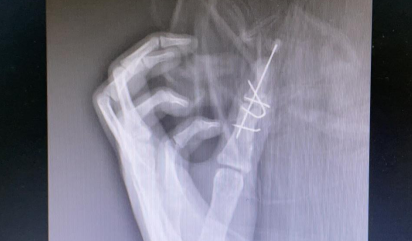

孙传伟医生将患者情况上报手外科大科主任朱辉,朱主任组织讨论手术方案,力求最大程度地改善患儿拇指外观和拇指指间关节功能。经过讨论,手术团队决定截骨矫形,左拇指尺侧拇指接近正常拇指为主拇指,桡侧拇指纤细为副拇指。 次日,朱主任手术团队为患儿进行了左拇指多指切除、截骨矫形内固定、肌腱韧带松解重建术,手术顺利。

术后即刻